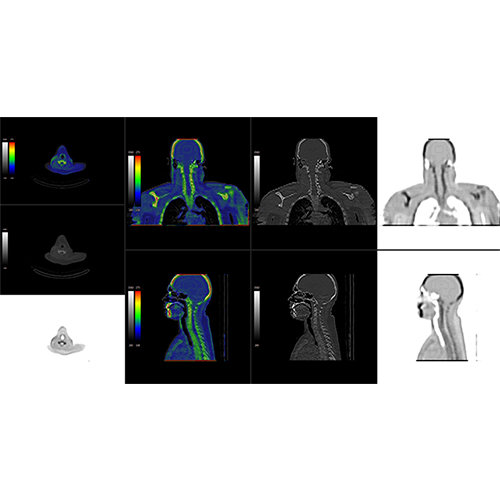

View X-Ray CT & MRI Scans Fast and Easily

Traditional multi-planar slicing

High-quality and fast 3D reconstruction and 3D rendering

Performs 3D reconstruction and volume rendering.

Multi-planar slicing.